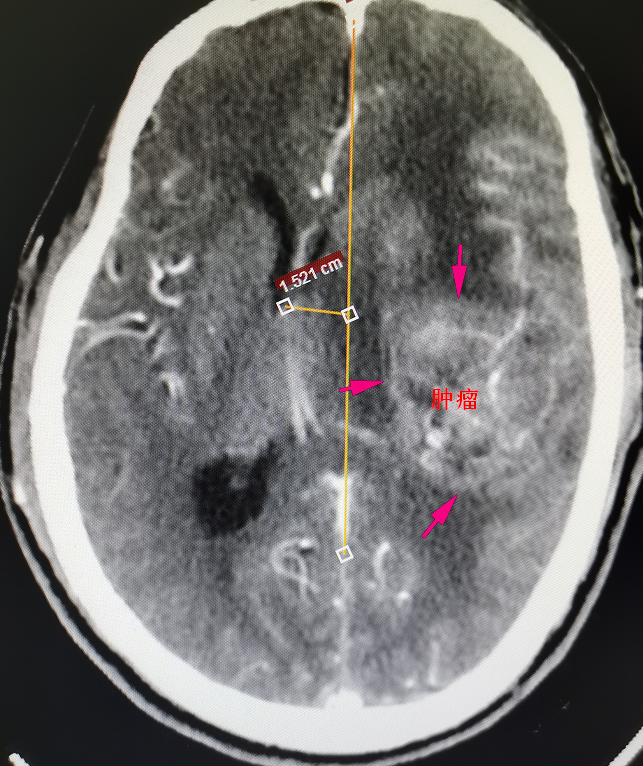

62岁的陈先生于今年曾因偏瘫在外院住院治疗无好转,且症状不断加重,甚至出现言语不清,小便失禁等异常。经影像检查(见图1)提示为左颞叶基底节区脑肿瘤,约6cm*5cm*5cm大小,比鹅蛋还要大,肿瘤位置深,向前累及外侧裂,包裹外侧裂部分血管,向下累及基底节区,肿瘤血供丰富,必须尽早实施手术治疗。

术前影像资料及手术标本,术前见中线结构严重偏移,侧脑室受压缩小,肿瘤周围水肿严重,肿瘤血供丰富

“由于肿瘤的位置侵犯外侧裂,影像学确定肿瘤包裹外侧裂的分支血管,有大脑中动脉以及枕动脉的多分支供血,紧邻肿瘤的还有过路血管。被包裹大的过路血管是不能损伤的,术中不小心损伤这段血管的话,大脑就会出现梗塞等一系列的并发症。”刘建民表示。